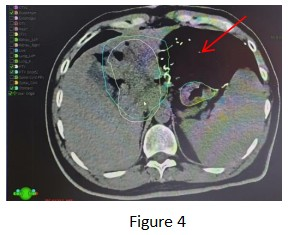

Follow-up treatment: After the completion of the initial treatment, due to the non-overlapping areas of PTV and PTVboost in Figure 4 being close to the stomach side and subject to the maximum tolerated doses of the stomach and duodenum, radical treatment doses were not administered.

After multidisciplinary consultation in our hospital and with the patient being fully informed and giving consent, we performed a technique pioneered in our hospital, namely exploratory laparotomy + placement of gauze pads to isolate the uninvolved organs (the red arrows in the figure all point to the imaging of the gauze pads).